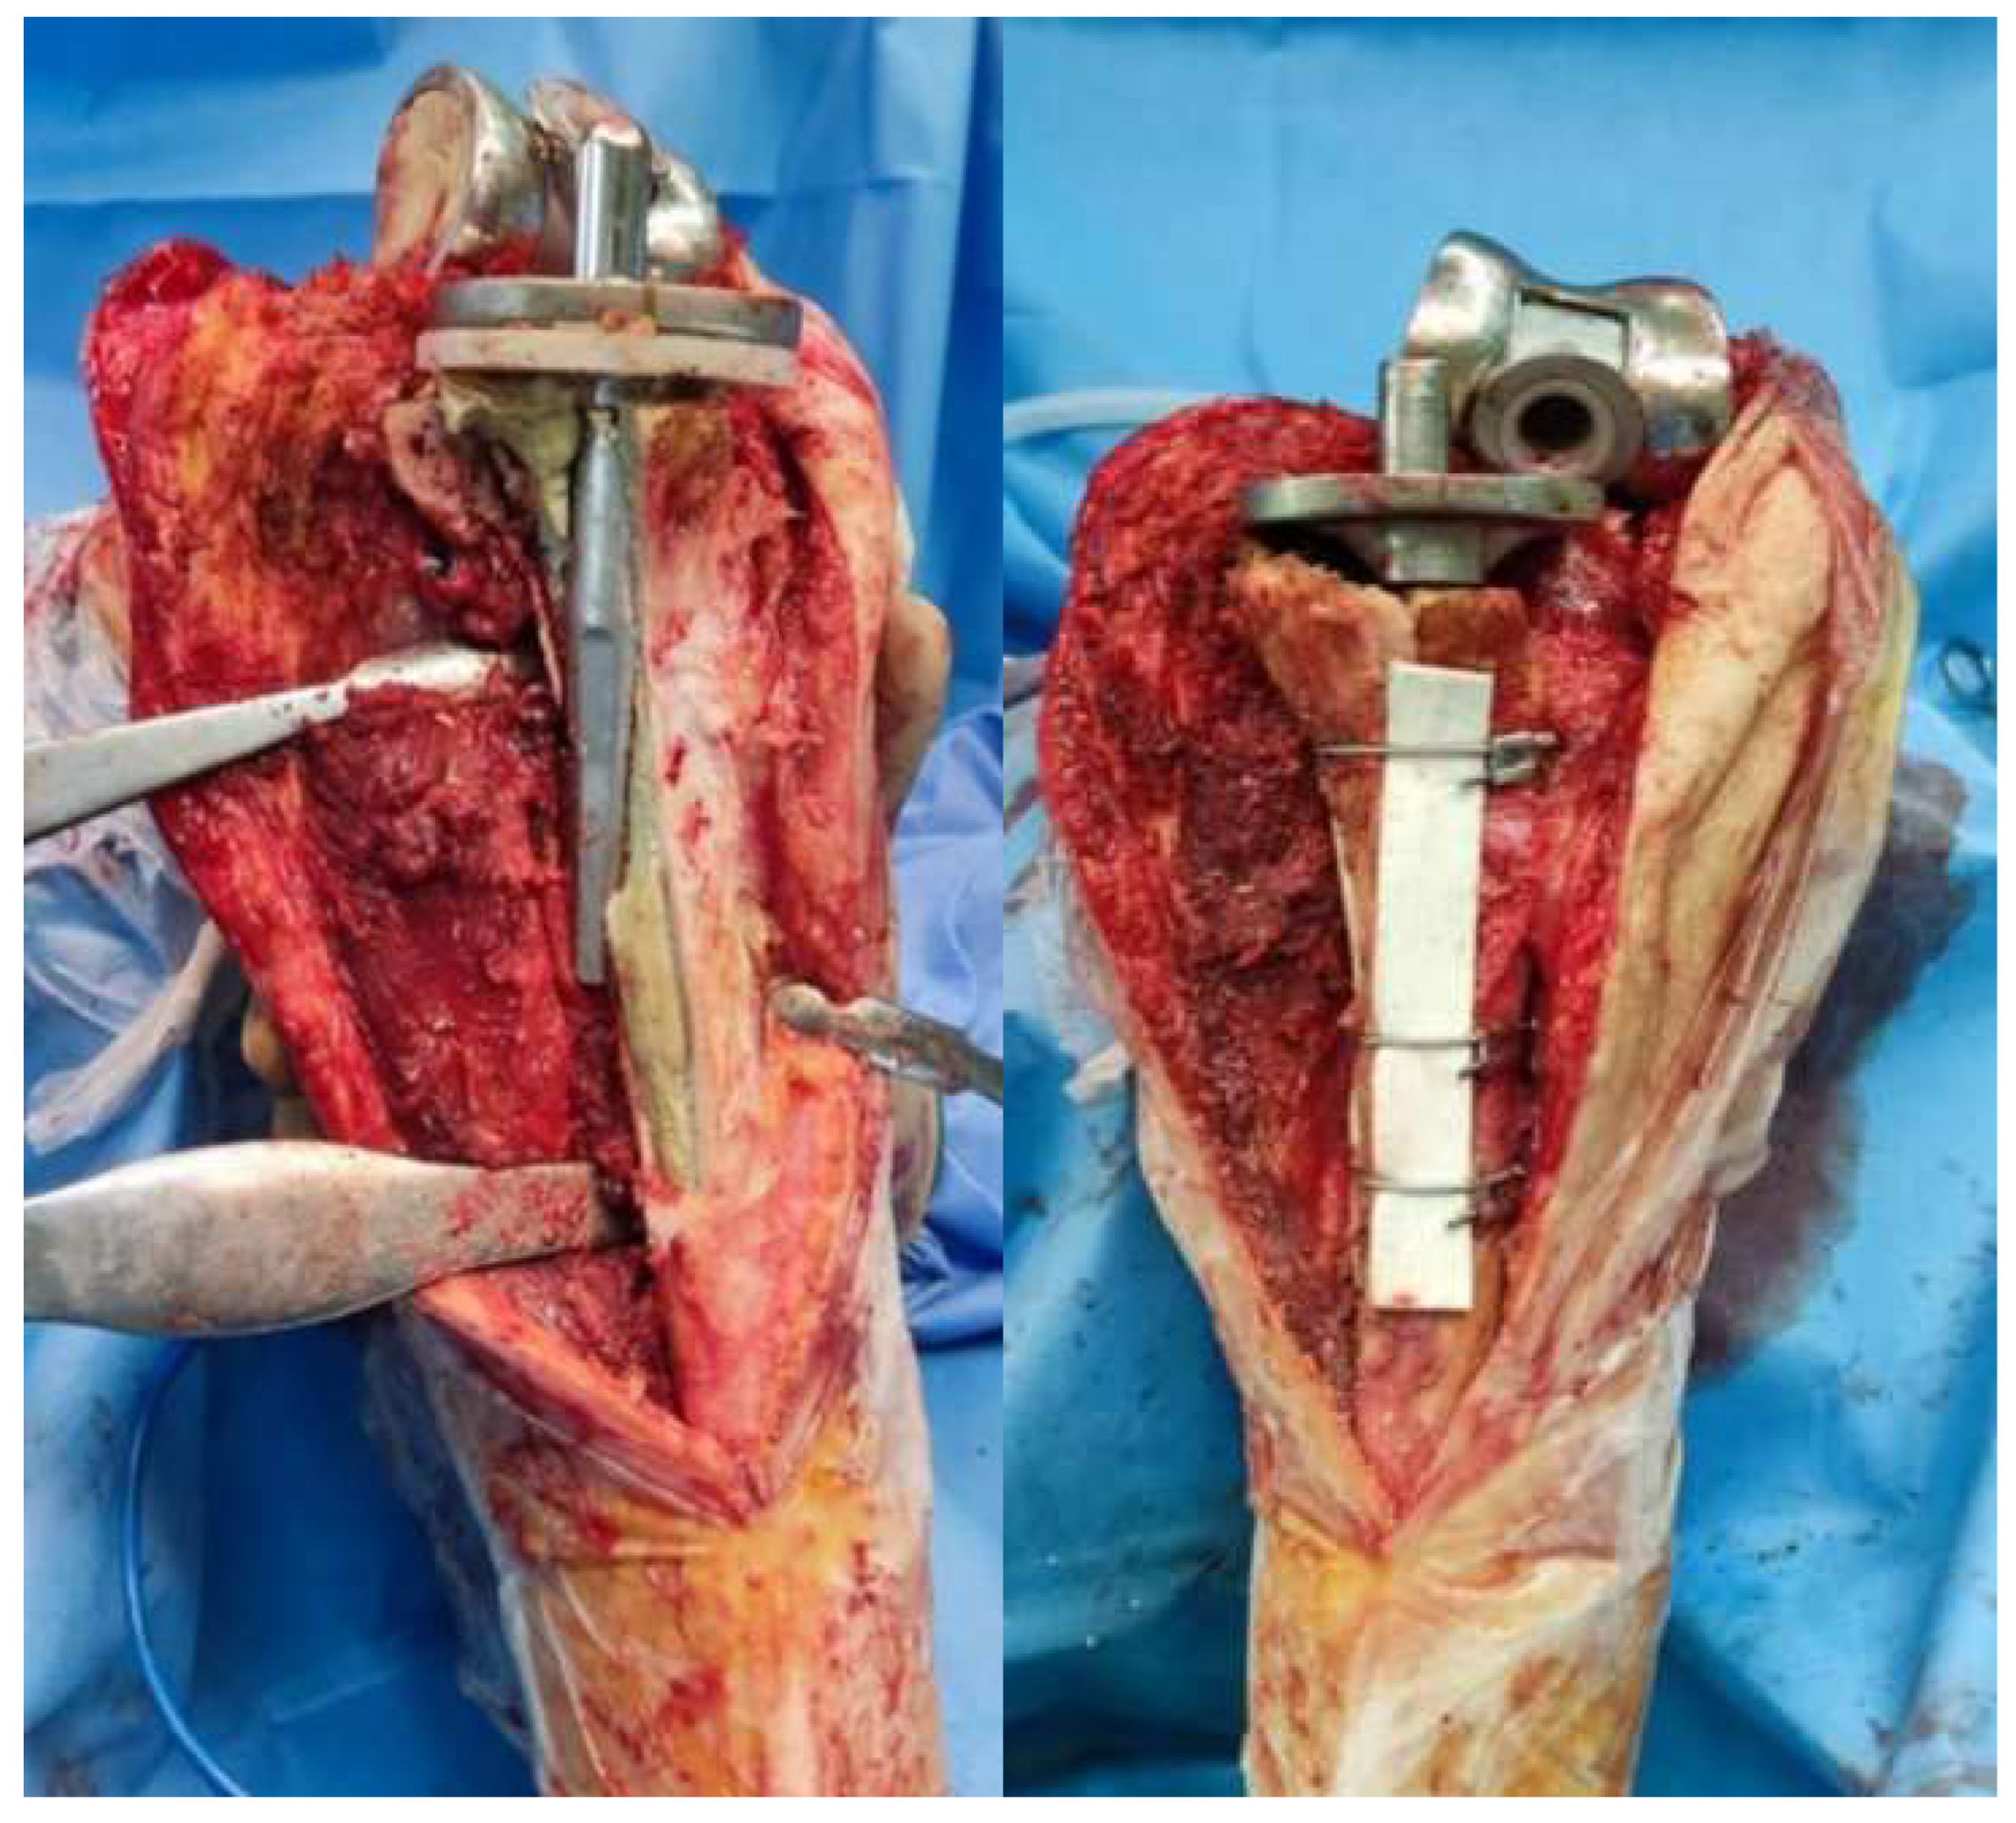

We retrospectively reviewed seven (7) hemophilic patients, with a mean age of 57.5 ± 1.50 years (95% confidence interval: 56–60 years) and mean body mass index (BMI) of 26.07 ± 0.67 kg/m2 (95% confidence interval: 25–27 kg/m2), who underwent ETTO for revision TKA in our department between 2015 to 2023. Preoperative diagnosis included (a) aseptic loosening of the femoral component but with a well-fixed tibial stem in four cases and (b) tibial component malposition that caused marked axial deformity in three cases (Figure 5). All seven patients initially considered for the study were included in the final analysis. None met the exclusion criterion—namely, the presence of active infection—at the time of evaluation, and all subsequently underwent surgery. The same surgical technique was applied in all seven cases. In Case 5 (Figure 5), the ETTO fragment was augmented with a bone graft prior to final reduction using cerclage wires, due to a bone defect attributed to prior stem perforation. A rotating hinge prosthesis was implanted in all patients, with an uncemented long stem. Clinical and radiological evaluation was performed at 6 weeks and 3, 6, and 12 months after surgery. Full baseline characteristics and outcomes are described in Table 1, Table 2 and Table 3.

All patients showed union at the osteotomy site 4 months after surgery, as confirmed by the presence of bridging callus formation on the lateral radiograph (Figure 6). Furthermore, there were no major complications related to the ETTO, such as infection, stem perforation or loosening, wire breakage, or periprosthetic fracture. There was only one case of delayed wound healing of the skin incision, probably attributed to the history of smoking and the presence of an inhibitor, which was managed with surgical debridement and antibiotic administration. No extension lag was recorded, and mean postoperative knee flexion was noted at 92.0° ± 2.58° (95% confidence interval: 8°–95°). In all cases, ETTO was proven to be a mandatory tool for performing a successful total knee revision.

Figure 4. Postoperative radiograph demonstrating the proper reduction of the bone flap (Case 3).